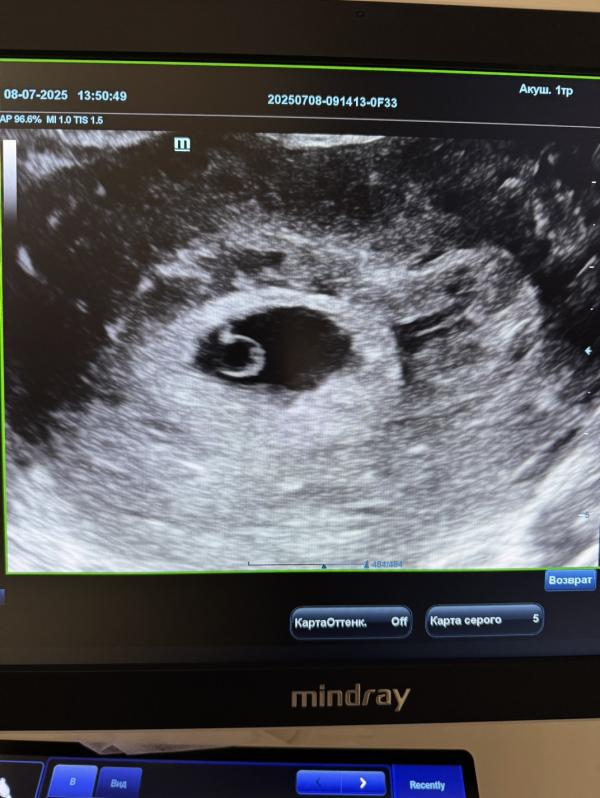

Что можно увидеть на УЗИ на 5 неделе беременности🤰

Матка: увеличена

В полости матки определяется ПЛОДНОЕ ЯЙЦО

Размер: 5–10 мм (соответствует 5 акушерской неделе).

Внутри плодного яйца визуализируется желточный мешок.

Диаметр: примерно 2–4 мм.

Эмбрион: на 5 неделе ещё не визуализируется, что является вариантом нормы.